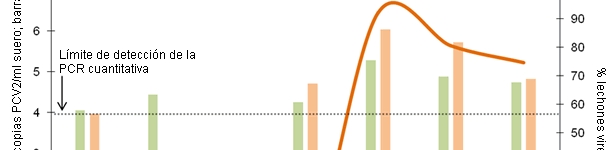

La situzione studiata in questo articolo è quella delle perdite causate da una minor crescita in svezzamento, quantificata da 13,1 € a 7,5 €/capo per i suini con carica virale di PCV2 alta e media, rispettivamente, con il metodo della PCRq individuale.

La forma più efficace di evitare le perdite produttive associate al PCV2 è che si eviti la viremia, stimolando un'immunità passiva oppure attiva che minimizzi la circolazione virale in allevamento.